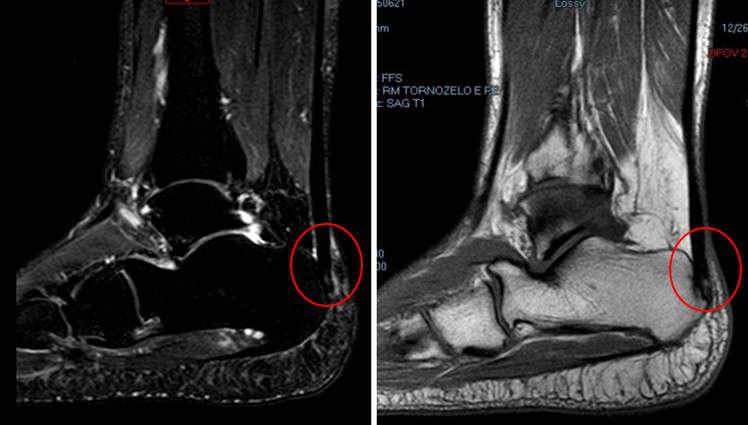

O tendão calcâneo ou tendão de Aquiles é um dos mais importantes e resistentes tendões do corpo, formado pela união dos músculos gastrocnêmio e sóleo. Saiba como é o tratamento da lesão: